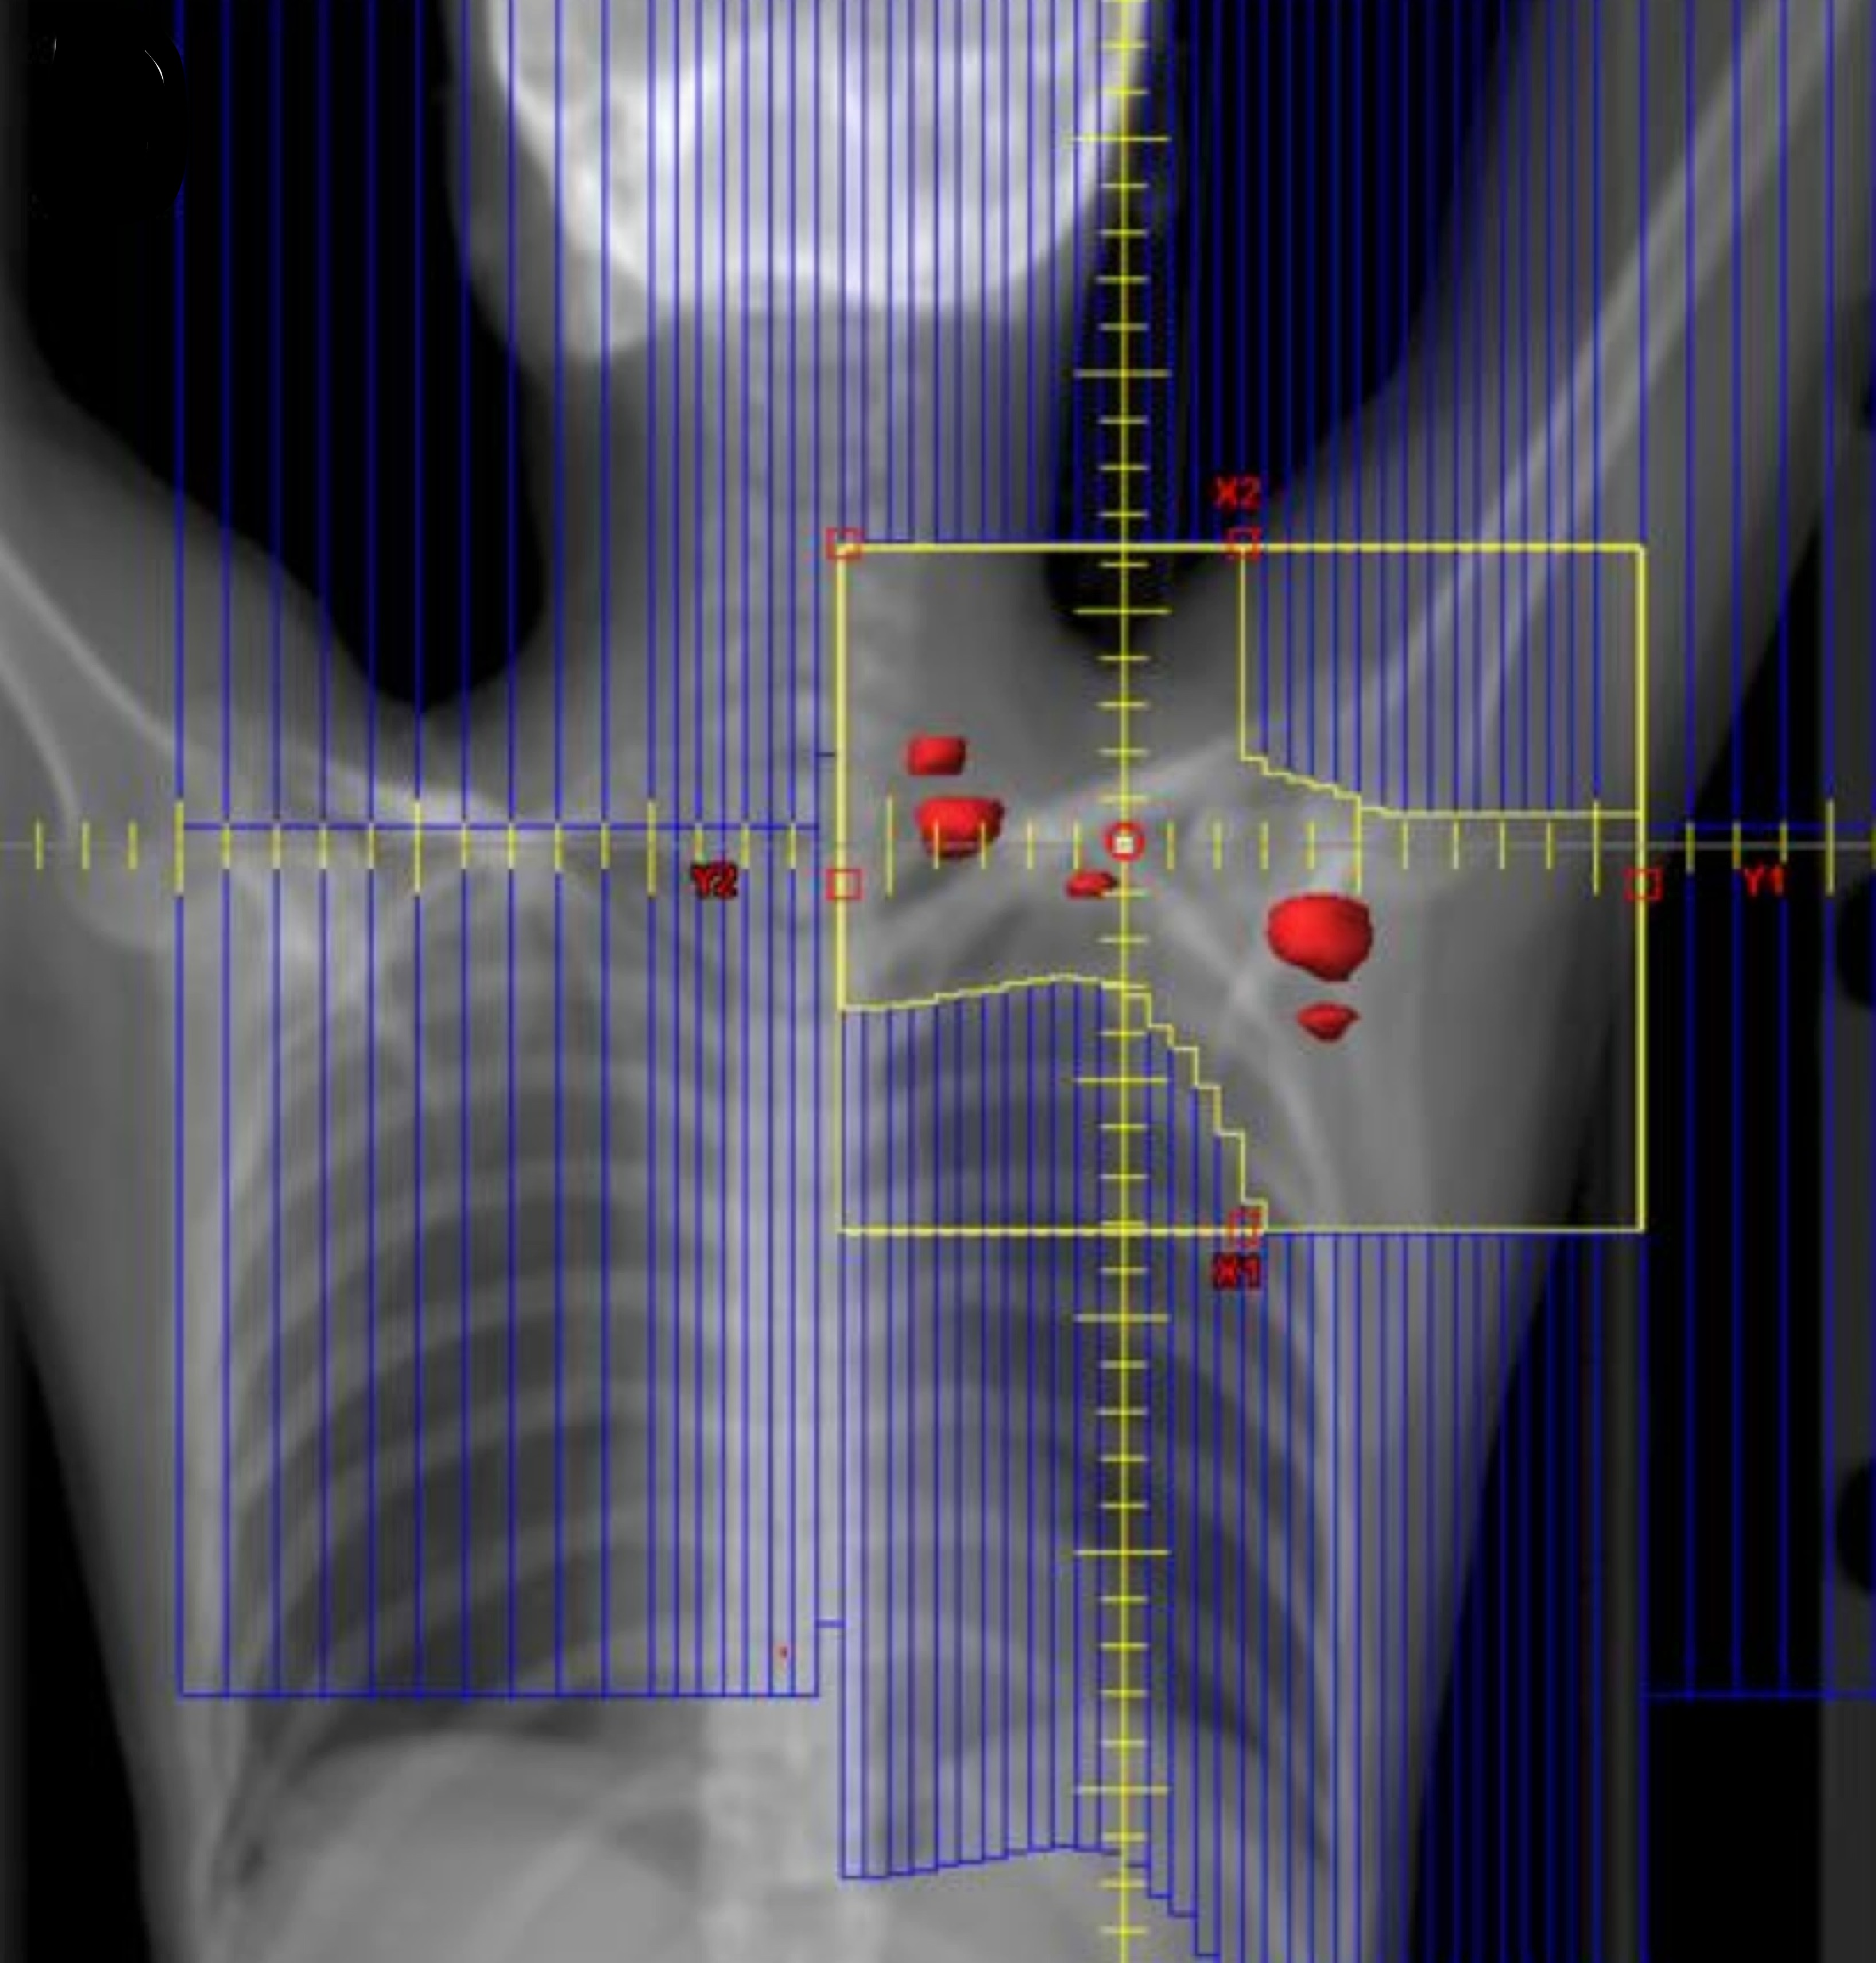

ISRT is most commonly recommended now as the most appropriate treatment field (Yaholom). Determining the optimum involved site definition may require incorporation of PET and MRI as well as pre-treatment and treatment planning CT to define the optimum volume.

Involved Site Radiation Field

• includes original extent of disease with margins to account for imaging limitations and disease specifics

• Recommended, based on GTV → CTV → PTV

• CTV=pre-chemotherapy extent of disease based on PET-CT

• CTV adjusted to exclude uninvolved normal tissues such as lung after tumor shrinkage

• CTV expanded to incorporate imaging/disease uncertainties

ISRT targets the site of the originally involved lymph nodes. This volume encompasses the pre-chemotherapy/pre-operative volumes. The fields are modified to spare adjacent uninvolved organs (lungs, bone, muscle, kidney), when the disease shrinks following chemotherapy. Concerns about the precise accuracy and localization of pre-treatment disease may lead to an expansion of the CTV based on clinical judgement. For NLPHL where radiotherapy is the sole modality treatment, a larger field should be considered.